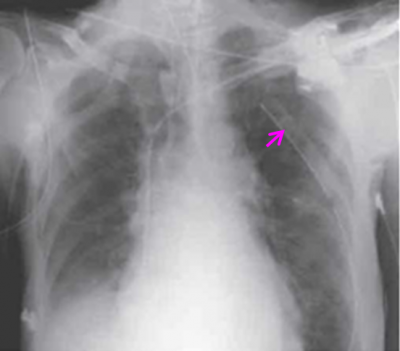

בהאזנה מעל הריאות ניתן לשמוע כניסת אוויר מופחתת, נשימה ברונכיאלית בצד הנפגע, ובניקוש - טימפניזם. בצילום חזה ניתן לראות תמט ריאה עם גבול ריאה המרוחק מדופן בית החזה (תצלום 12.16) המיצר ללא סטיה וגובה הסרעפות שווה, כמו כן ניתן למצוא אמפיזמה תת-עורית (תצלום 13.16). ממצאים אלה נראים ברור יותר ב-CT חזה.

בצילום חזה של נפגע עם חזה אוויר בלחץ נראה בנוסף לסמני חזה אוויר גם דחיקה של המייצר לכיוון הנגדי וגם דחיקה של הסרעפת כלפי מטה (תצלום 14.16).